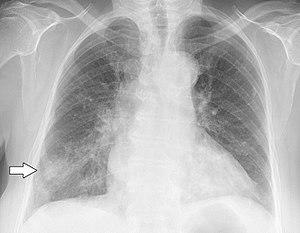

Chest X-ray of a patient who first had influenza and then developed Haemophilus influenzae pneumonia, presumably opportunistic | |